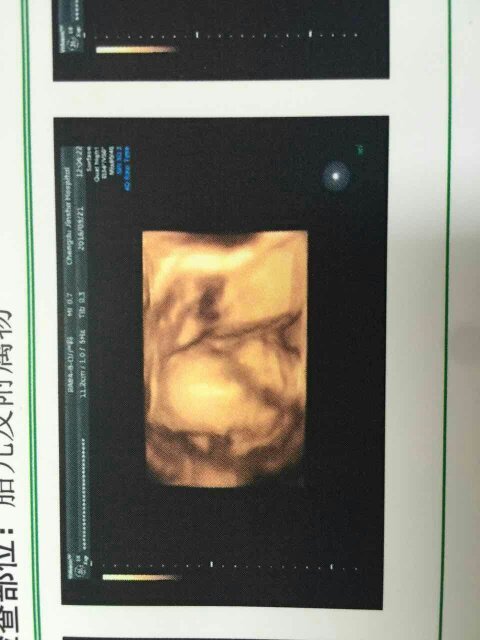

帮我看看吧,是男孩还是女孩,就是好奇绝对没有重男轻女的理想,怀孕刚好22周就做了四维!!